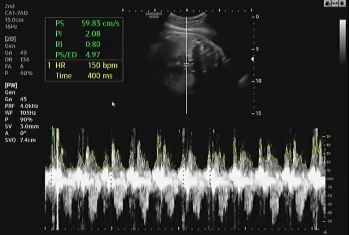

임신 39주 4일 차 병원에 내원해 초음파를 확인했다. 지난번에 이어 큰 이상이 없어 2주 뒤에 내원했는데 다행히 태아도 그동안 건강함을 알려주듯 초음파를 보는 내내 열심히 움직였다.

자궁경부의 길이는 지난번에 비해 얇아졌지만 여전히 아기는 골반에 위치하지 않고 위에서 놀고 있다고 했다. 자세를 잡은 지는 몇 주가 넘었지만 내려올 생각이 없이 열심히 놀기 바쁜 아기에게 얼른 내려오라고 이야기했는데 엄마의 말을 들어줄 생각이 없는 것 같다.